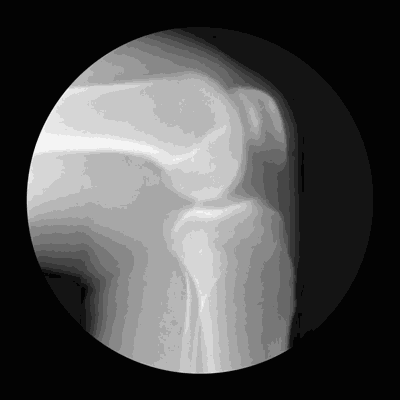

什么是半月板?

半月板是膝关节内的新月状(C型)纤维软骨结构 , 有缓冲作用 , 可以稳定膝关节 , 减轻膝关节负荷压力 。 膝盖疼痛、肿胀、发出响声等 , 是半月板损伤的典型症状 。